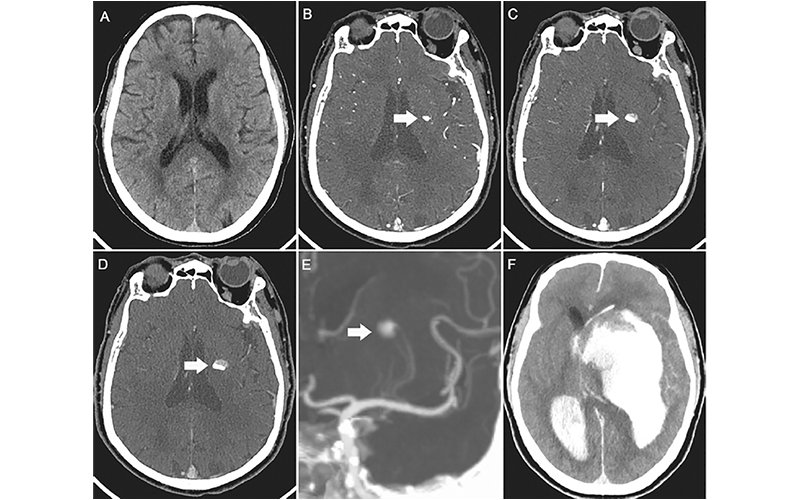

Images in a 73-year-old man with acute left-sided weakness. (A) Axial noncontrast CT image of the head shows no intracerebral hemorrhage. (B) Arterial phase CT angiogram obtained 192 seconds later, after administration of contrast material, demonstrates focal enhancement in the left basal ganglia (arrow). (C, D) CT angiograms obtained in the (C) second and (D) third phases, with delays of 39 seconds and 38 seconds, respectively, highlight the active expansion of the intracerebral hemorrhage with the blood-contrast level (arrows). (E) Coronal maximum intensity projection image reveals that the bleeding was located near the distal ends of the lenticulostriate arteries (arrow). (F) Follow-up noncontrast CT image obtained 1 hour after the third phase CT angiogram shows massive enlargement of the hematoma, intraventricular hemorrhage, hydrocephalus, and subfalcine herniation. https://doi.org/10.1148/radiol.229031 ©RSNA 2022

The second runner-up was a tie between two articles. The first, “CT of Ongoing Intracerebral Hemorrhage,” is by Chun Ma and Yi Zhou with imaging that captured the rapid evolution of a progressively expanding intracerebral hemorrhage in a 73-year-old man.